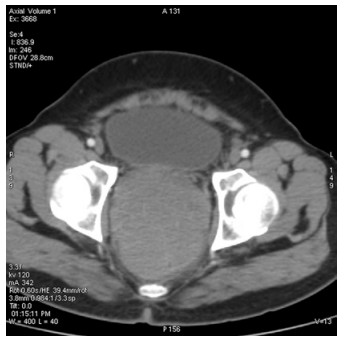

Abstract: Rectal malignancy is usually symptomatic due to its location, and most of the time presents with pain and bleeding due to its growth and ulceration. It is difficult to identify the primary as carcinoma or lymphoma based on symptoms only, as both have a similar presentation. As it presents the rarest form of histology, non-Hodgkin's lymphoma in the rectum is still difficult to diagnose initially, and its treatment is debatable. We describe the case of a 49-year-old male from Bangladesh with the same presentation. His treatment was delayed for more than a month as immunohistochemistry and staging delayed the final diagnosis. The disease was diagnosed as stage IE with the help of a positron emission tomography (PET)-CT scan, and due to the local progression the patient had a massive rectal bleeding that needed an urgent intervention. Radiotherapy was applied to stop the bleeding. Hypofraction followed by a conventional fraction of external beam radiotherapy (EBRT) with a total of 40 Gy was applied. Post-EBRT digital rectal examination showed no residual except scaring, and a PET scan was also negative for residual disease. Due to uncertainties and lack of any precious guideline, 6 cycles of adjuvant chemotherapy with the R-CHOP schedule were also completed. Without surgery, the combination of EBRT and chemotherapy helped to preserve the organ, and the patient has been disease free for more than 2.5 years since his treatment.